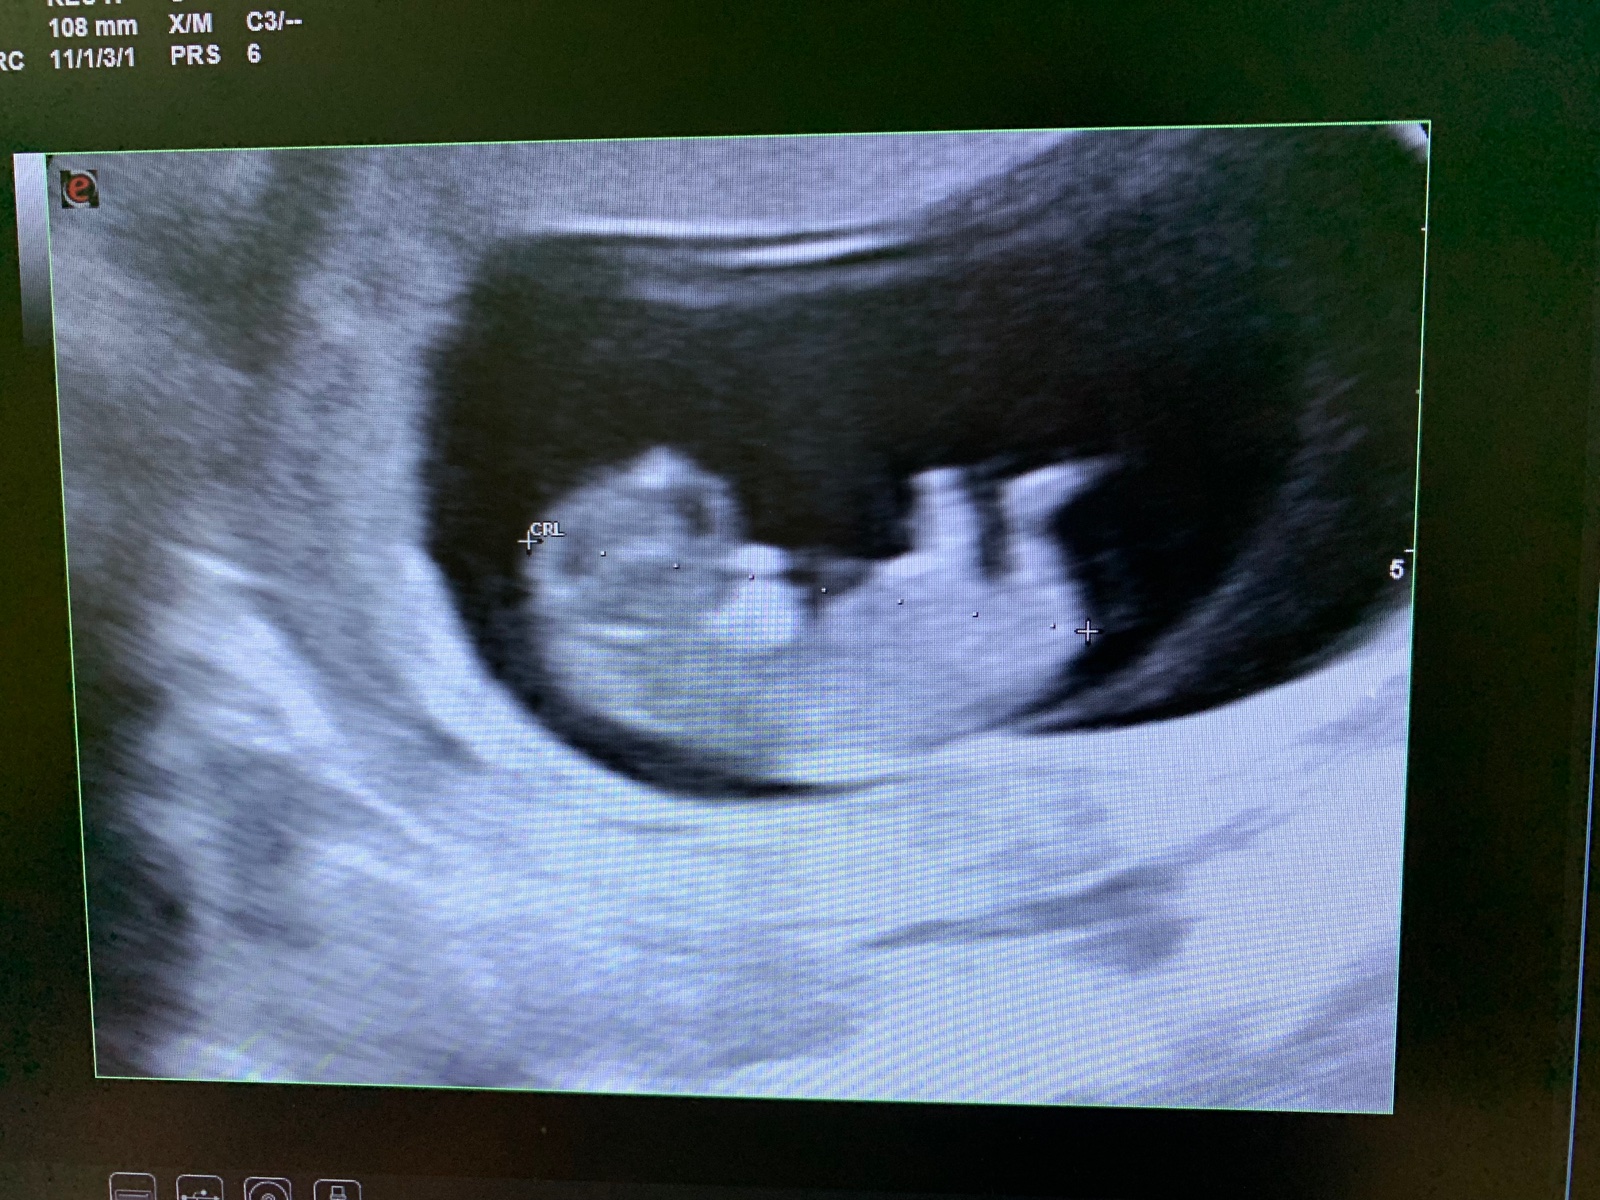

Chlapec alebo dievča. Čo tipujete?

toto je take 12 t babatko v brusku....

Ked tu vidim nejaku fotku z ultrazvuku a k tomu otazku o pohlavi, tak si stale pripadam ako debil, lebo casto sa mi stava, ze nedokazem identifikovat ani kde je dieta, nie to este pohlavie. Tuto aspon vidim dieta a ze ma dve nohy... 🙂